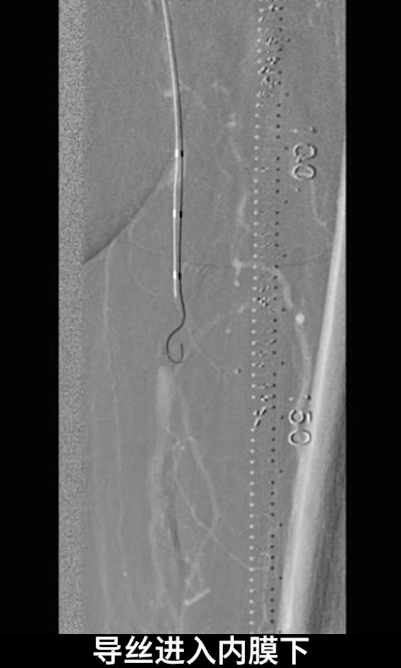

首先尝试顺行通过股浅动脉闭塞段,导丝进入内膜下,开通失败;遂改为逆穿策略,以支撑导管配合V18导丝逆行通过股浅动脉闭塞段,最终与近端股浅动脉真腔成功对接,建立安全操作轨道。